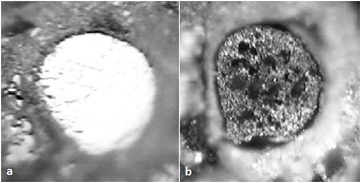

From purely visual analysis, in the PBS-only samples, the electrode surfaces polished to 1 µm smoothness displayed roughening after 1 d, pitting after 2 d, and full recession from the initial surface after 6 d to a depth of >4 µm, similar to the reports by Prasad. In the in vivo studies, the W receded within its insulation 24 ± 8 µm after 87 d of implantation (figure 7). Similar results were reported by others (figure 8). No oxide layer was present in either case, contradicting claims of oxide passivation due to localised acidosis.

Figure 7. Optical photographs of 50 µm nominal diameter W electrode. (A) Before immersion in PBS (polished); (B) after 23 d of immersion, with evidence of corrosion: surface roughening, pitting, and dark oxidic patches [13].

Standard image High-resolution imageFigure 8. SEM images of recording tips of 50 µm diameter W microelectrodes encased in polyimide implanted for 7 d. L: pre-implant; R: post-implant. Corrosion has occurred, indicated by a darkening, loss of volume, and a change in surface morphology [92].